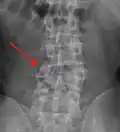

A burst fracture of L4 as seen on plane X ray

A burst fracture of L4 as seen one plane X ray